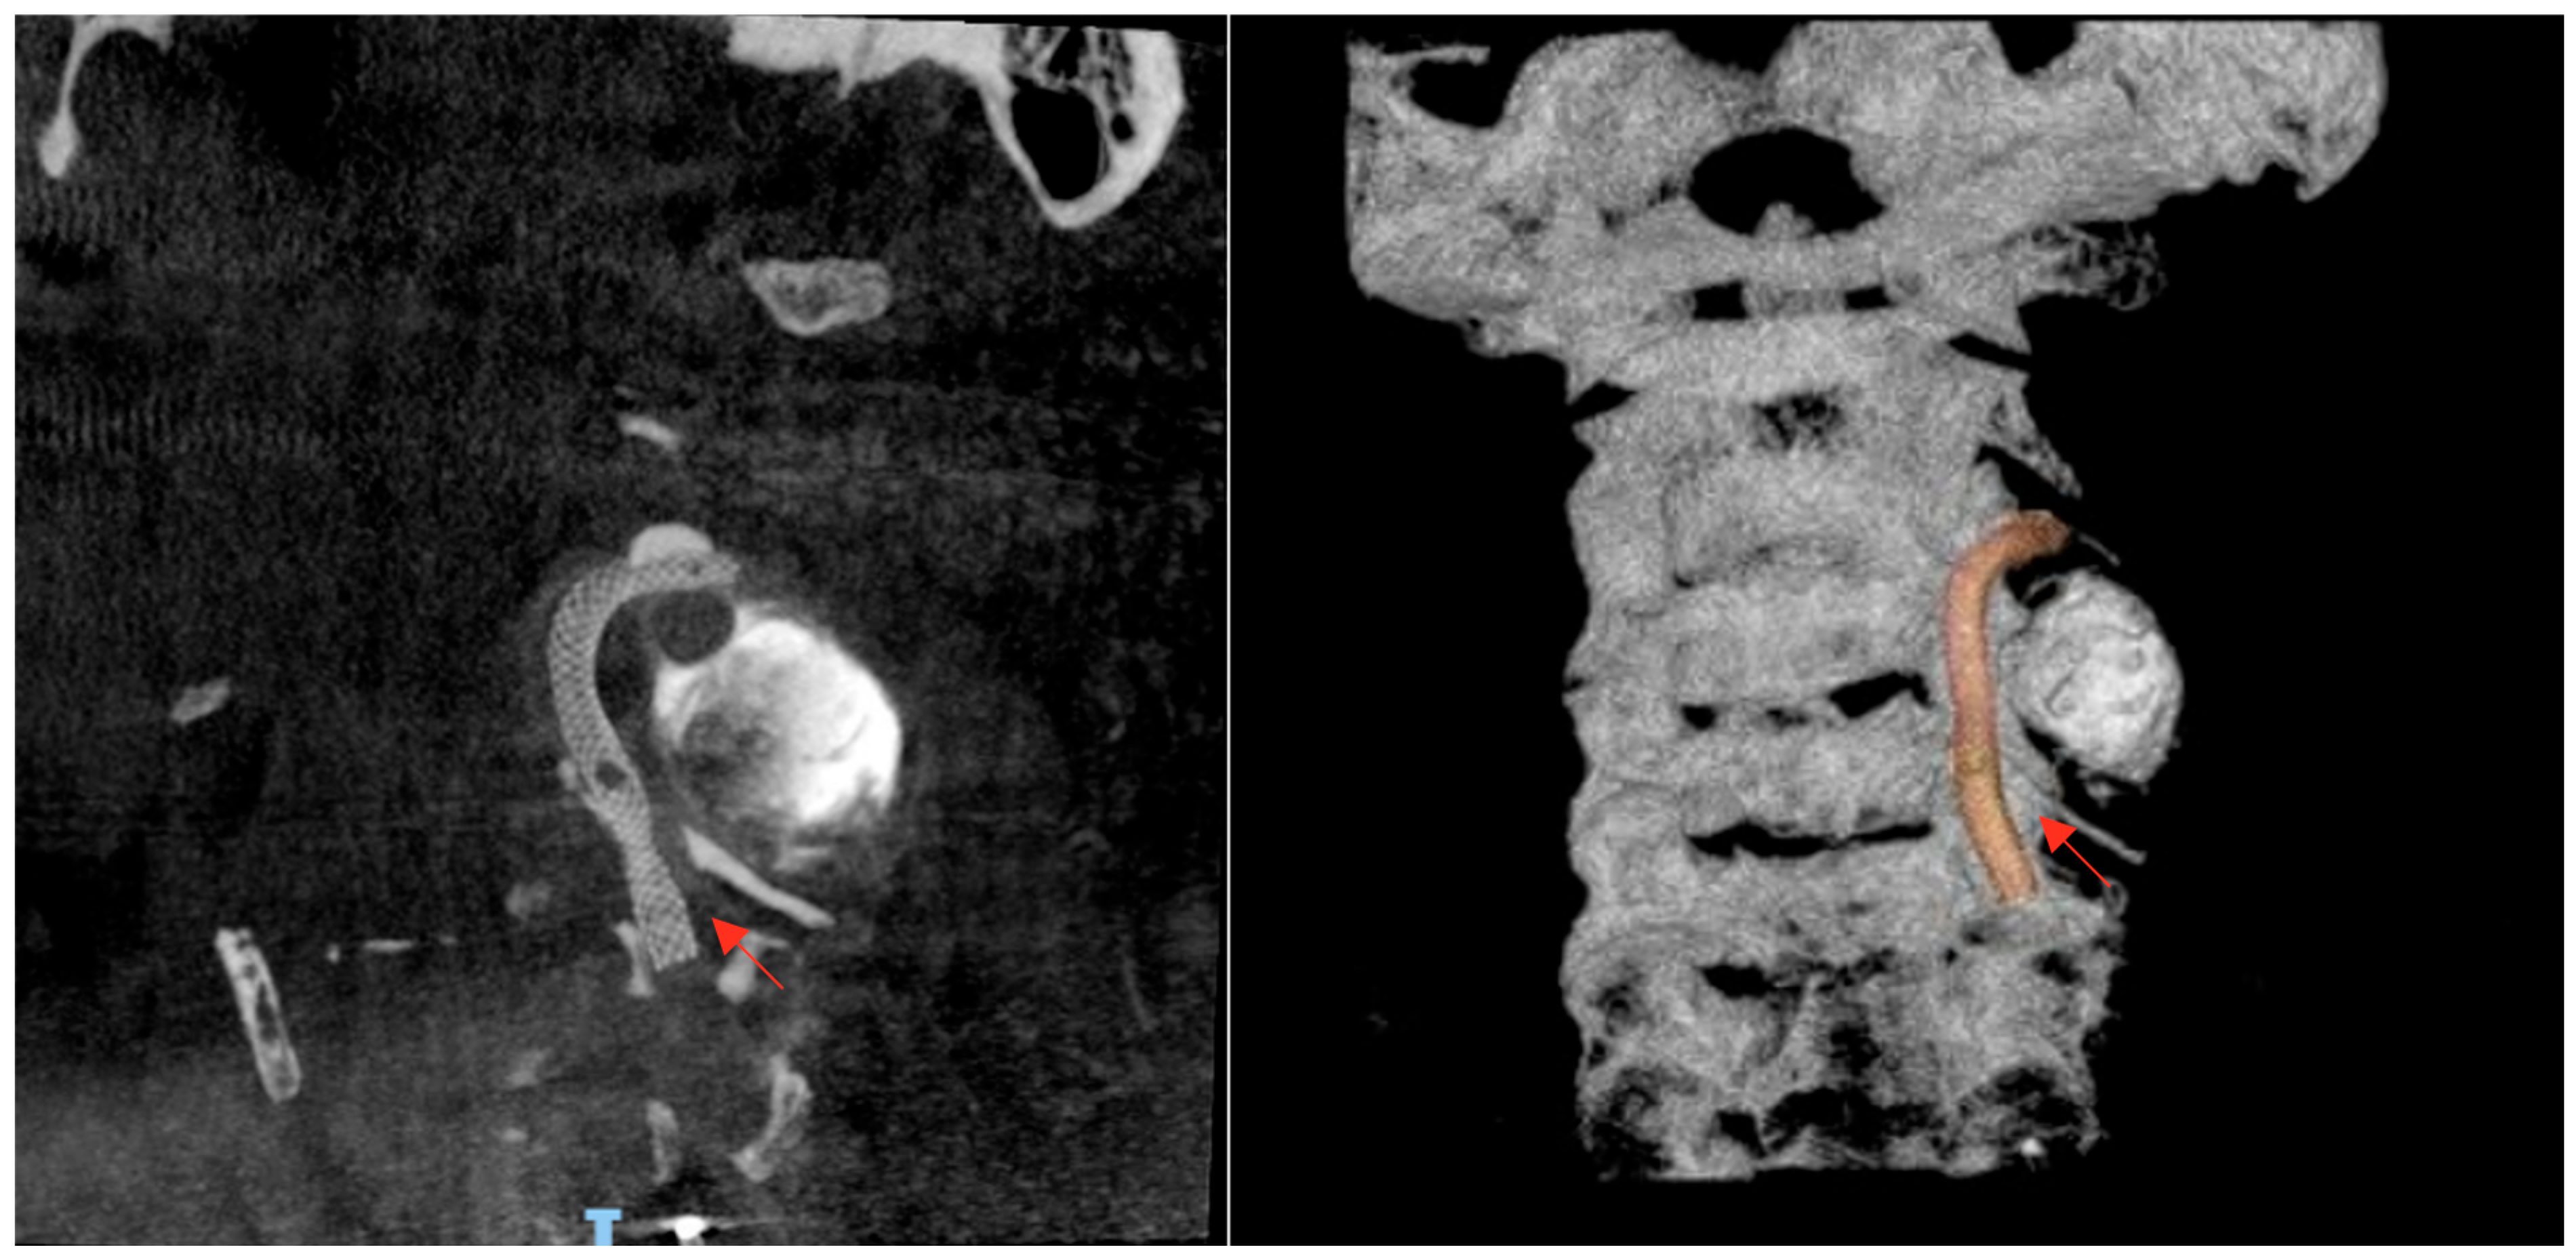

Subsequent computed tomography angiography (CTA) of the neck and cerebral vessels demonstrated a tortuous left vertebral artery with a fusiform aneurysm in the V2 segment measuring 10 × 14 mm, with an associated mural defect and active contrast extravasation into a perivertebral collection of 34 × 24 mm (Figure 2).

Figure 2. Contrast-enhanced CT angiography of the neck and cerebral vessels, axial view (A), sagittal view (B), and coronal view (C), performed after intravenous administration of 100 mL of non-ionic iodinated contrast medium (Iohexol, Omnipaque® 300 mg I/mL, injection rate 3–4 mL/s). Image acquisition was performed during the arterial phase using a bolus-tracking technique (approximately 20–25 s after injection, triggered when the contrast density in the aortic arch reached ≥120 Hounsfield units). The study demonstrates a tortuous left vertebral artery with fusiform aneurysmal dilation of the V2 segment, measuring approximately 10 × 14 mm. A focal mural defect is identified, with active contrast extravasation into a contained perivertebral hypodense collection (34 × 24 mm). The aneurysmal dilation is marked by the red arrow, while the mural defect is indicated by the arrowhead. Source: patient’s medical record, published with prior authorization.